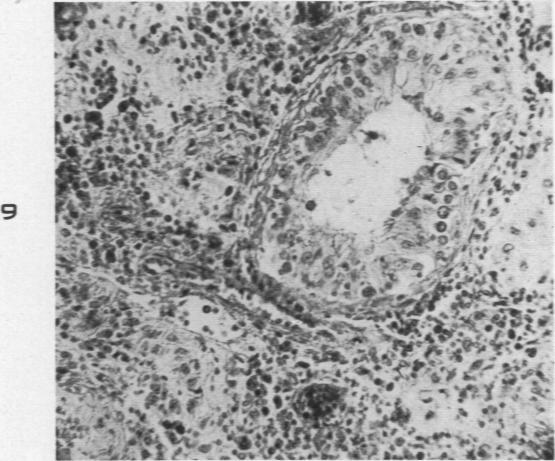

The Histopathology of Acute Mumps Orchitis.

Am J Pathol. 1947 Jul;23(4):637-51.